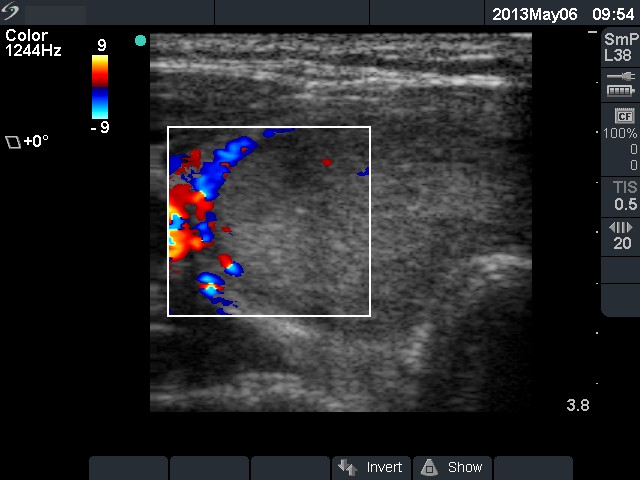

Ultrasonography: the thyroids were echonormal. There was an echonormal nodule occupying almost the entire right lobe. The lesion displayed a halo sign, cystic degeneration and presented perinodular blood flow.

5 sessions of sclerotherapy were performed. We demonstrate the 1st and 4th session.